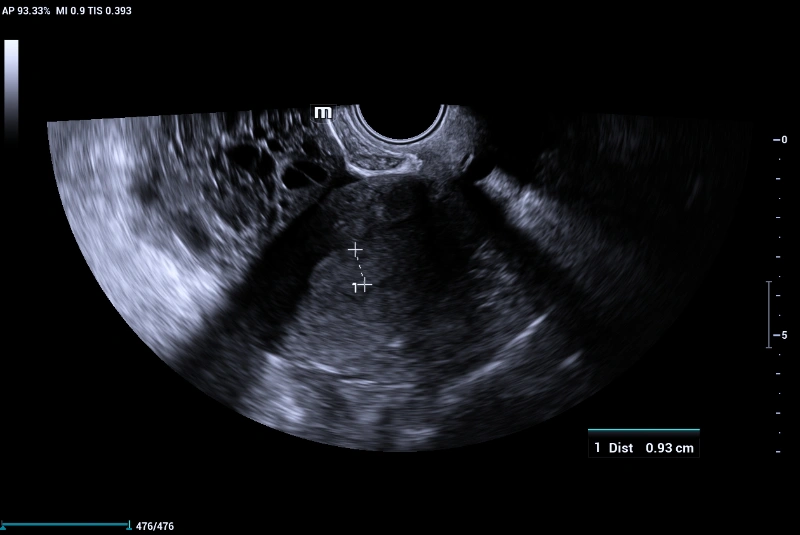

Using Mindray Nuewa I9 Elite edition transvaginal volume transducer DE 11-3Ws, the following findings were noted:

• The left ovary harbors a multi-locular solid mass lesion measuring about 78x63x66 mm at maximum dimension showing multiple irregular (more than 10) locules giving the characteristic Swiss cheese appearance that was well appreciated on volume reconstructed images using Mindray’s iLive pro and Hyaline features.

• On color doppler interrogation on, marked internal vascularity was noted (color score 4). Combination of power doppler and 3D volume ultrasound helped in accurately assessing the mass vascularity and color scoring.